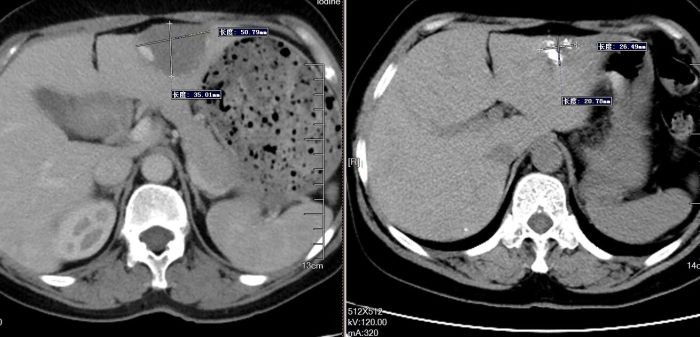

该患者5年前体检发现肝血管瘤,近期复查显示瘤体较前增大。为避免传统外科手术带来的较大创伤与较长恢复期,经德江县人民医院介入科团队评估,为其施行了经导管肝动脉栓塞术。手术仅通过右侧股动脉一个约2毫米的穿刺点,将微导管精准送至肝脏血管瘤的供血动脉,注入栓塞剂,使瘤体因缺血而逐渐萎缩,从而达到治疗目的。

肝血管瘤是常见的肝脏良性肿瘤,虽多数生长缓慢、无明显症状,但体积较大时仍存在破裂出血的风险,犹如体内的“定时炸弹”。与传统开腹手术相比,介入栓塞术具有创伤小、痛苦轻、恢复快、住院时间短的显著优势。患者术后仅出现轻微腹痛和短暂抖动反应,经对症处理后迅速缓解,术后第3天即达到出院标准。治疗期间无需开刀、无需全身麻醉,术后仅需右下肢制动12小时、卧床24小时,极大减轻了患者的生理负担与心理压力。